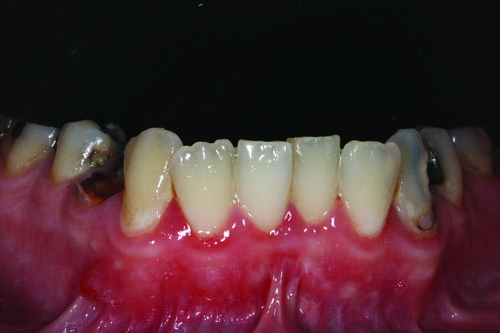

For this 31-year-old patient, an inability to afford or prioritize the care and treatment of his visibly damaged and decayed teeth—combined with a longtime fear of going to the dentist—led to a mouthful of severely deteriorated dentition and a history of chronic periodontal inflammation, multiple recurrent decay and incomplete treatments.

Over the years, friends, family members and co-workers would occasionally comment about his smile and ask what he was doing to fix it. Although he had regular cleanings every six months until he was in middle school (when his mother was in charge of his appointments), as he grew older he didn’t develop a regular brushing habit. As the cavities developed more frequently—and despite the use of nitrous oxide—his dental visits became increasingly unpleasant.

Fig. 2: Close-up retracted facial view of the patient’s upper and lower arches reveals extensive decay, missing teeth and obvious gingival inflammation.